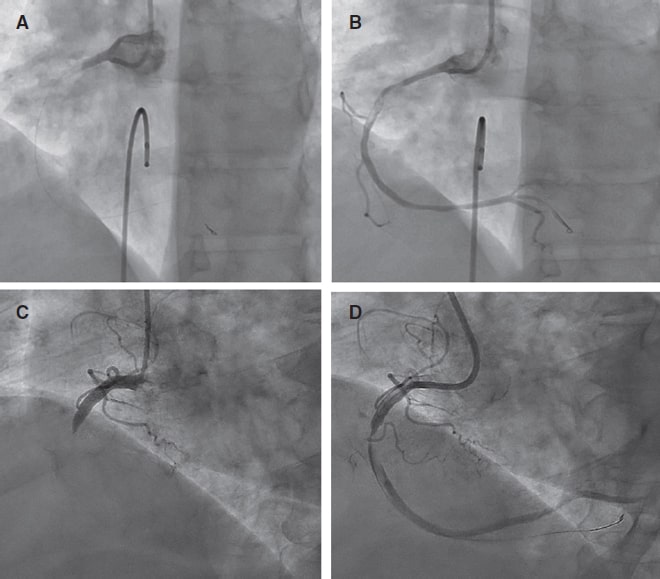

Introduction and objectives: Distal radial access (DRA) for coronary procedures is currently recognized as an alternative to conventional transradial access, with documented advantages primarily related to access-related complications. However, widespread adoption of DRA as the default approach remains limited. Therefore, this prospective cohort study aimed to present our initial experience with DRA for coronary procedures in any clinical settings.

Methods: From August 2020 to November 2023, we included 1000 DRA procedures (943 patients) conducted at a single center. The study enrolled a diverse patient population. We recommended pre- and postprocedural ultrasound evaluations of the radial artery course, with ultrasound-guided DRA puncture. The primary endpoint was DRA success, while secondary endpoints included coronary procedure success, DRA performance metrics, and the incidence of access-related complications.

Results: The DRA success rate was 97.4% (n = 974), with coronary procedure success at 96.9% (n = 969). The median DRA time was 40 [interquartile range, 30-60] seconds. Diagnostic procedures accounted for 64% (n = 644) of cases, while 36% (n = 356) involved percutaneous coronary intervention (PCI), including primary PCI in 13% (n = 128). Pre-procedure ultrasound evaluation and ultrasound-guided DRA were performed in 83% (n = 830) and 85% (n = 848) of cases, respectively. Access-related complications occurred in 2.9% (n = 29).

Conclusions: This study shows the safety and feasibility of DRA for coronary procedures, particularly when performed under ultrasound guidance in a diverse patient population. High rates of successful access and coronary procedure outcomes were observed, together with a low incidence of access-related complications. The study was registered on ClinicalTrials.gov (NTC06165406).